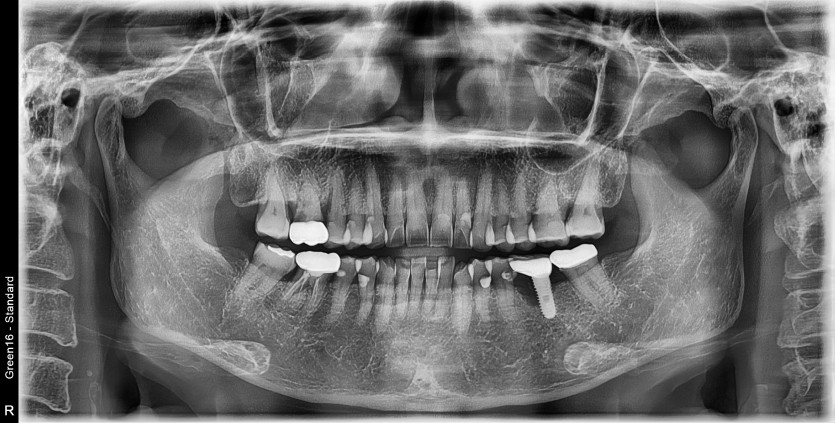

#36 타병원 임플란트 뼈이식 + 재식립